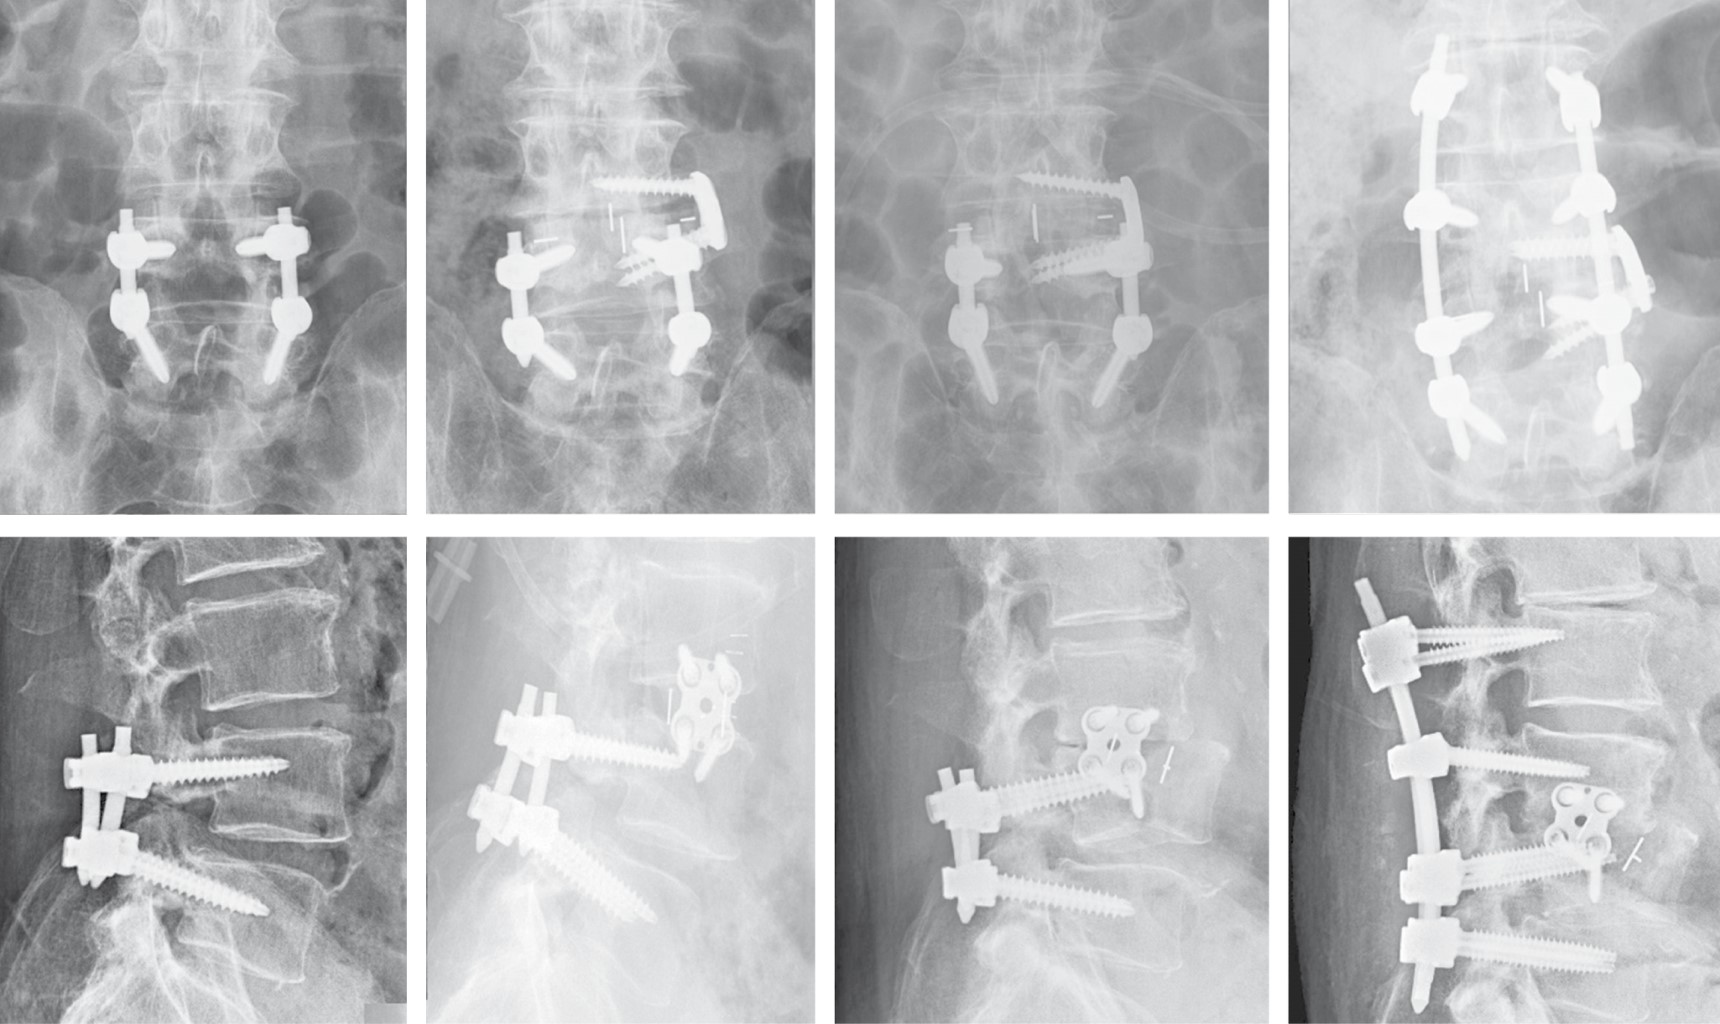

Como complicaciones tardías locales mayores, cabe señalar que no se encontró ningún caso de fístula de líquido cefalorraquídeo o seudomeningocele, ninguna fibrosis perirradicular, hernia abdominal ni infección. Pero se recogieron dos casos de fractura vertebral, una recidiva clínica y una movilización de caja, sin encontrarse diferencias estadísticas entre los grupos. Fractura L4: paciente varón de 85 años con artrodesis lumbar L4-L5 TLIF, hace años que fue intervenido en Noviembre de 2016 realizándose LLIF L3-L4 (PEEK), presenta fractura de L4 en Enero de 2017 (dos meses postquirúgicos) realizándose mediante abordaje bilateral de Wistle retirada de material TLIF previo y artrodesis con tornillos pediculares L2 a L5 (Figura 4). Fractura L3: Paciente mujer 67 años con artrodesis lumbosacra L4-S1 previa que fue intervenida en julio de 2017 realizándose LLIF L3-L4 (titanio), presenta fractura de L3 en Marzo de 2018 que fue intervenida realizándose en un primer tiempo lateral colocación de caja de corrección hiperlordótica. En un segundo tiempo mediante abordaje posterior, extracción de tornillos y barras y se amplía la artrodesis posterior D11-S1 (Figura 5). Movilización caja: mujer de 48 años con antecedentes de artrodesis L5-S1 se intervino en Julio de 2017 realizándose LLIF L4-L5 (PEEK) mediante técnica stand-alone, a las cinco semanas de la cirugía comenzó con un importante dolor lumbar irradiado a miembro inferior izquierdo. El estudio de imagen demostró una movilización mayor de 10 mm. Como tratamiento quirúrgico se procedió a la retirada de la caja por la misma vía transpsoas y ante la imposibilidad de colocar nuevo implante debido a la rotura parcial de la caja y al alto riesgo de lesionar el nervio femoral se decidió rellenar el espacio intersomático mediante injerto con DBM (Figura 6). Recidiva: paciente varón de 82 años con artrodesis lumbar L4-L5 PLIF, hace años que fue intervenido en Julio de 2017 realizándose LLIF L3-L4 (PEEK), presenta recidiva clínica (dolor lumbar y radicular) en Diciembre de 2017 (cinco meses postquirúrgicos), se realizó mediante abordaje posterior descompresión mediante laminectomía L3. Cuatro pacientes (13.8%) fueron reintervenidos (con retirada del implante (movilización y una fractura) y se añadió cirugía de fijación posterior (con descompresión en el caso de la recidiva). El estudio comparativo de las complicaciones no evidenció diferencias respecto al tipo de caja (p = 0.33) ni con respecto a la necesidad de reintervención (p = 0.624) ni a la de retirada de la caja (p = 0.523) (Tabla 5).

Figura 4